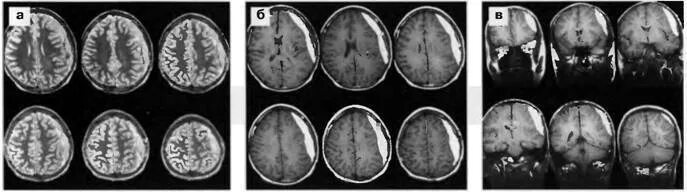

Кровоизлияние в мозг у новорожденного степени